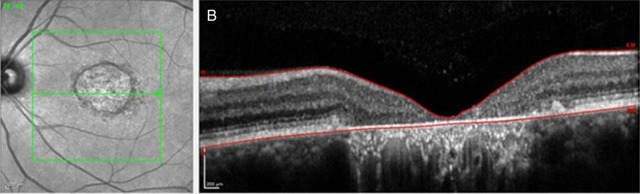

研究表明,SD-OCT 可以监测 STGD1 的视网膜体积下降情况,但是需要手动矫正视网膜界限识别错误等程序错误,如图 1。作者认为,视网膜厚度和体积的测量包括视网膜色素上皮层可能更有利于监测 STGD1 的萎缩进程。

图 1 左侧为共焦激光扫描检眼镜图像,右侧为相应横截面的单个 B 扫描。图 A 箭头所指部分为软件对视网膜内外界限的识别错误;图 B 为手动矫正错误后。